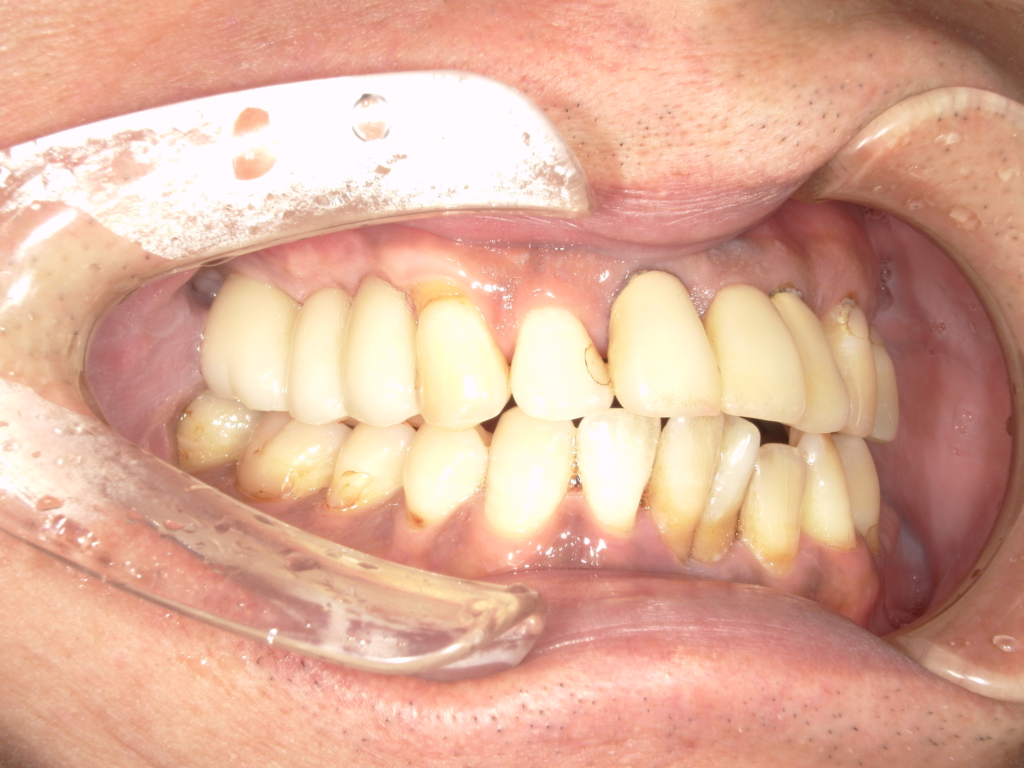

左右の上顎にインプラントを埋入しました。左下にインプラントを埋入しました。上部構造物は、全てセラミックで作ってあります。

治療前

治療後